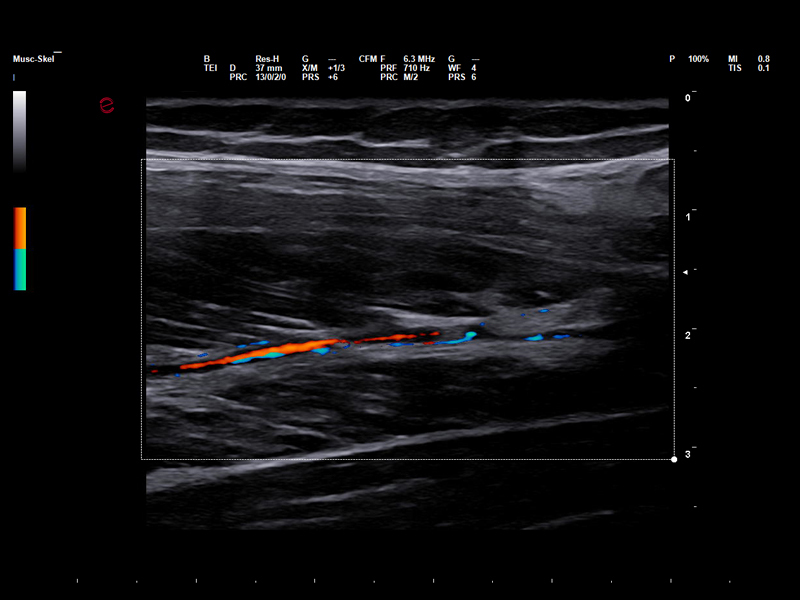

Microvascular insights in sports medicine

In sports medicine, Power Doppler allows for accurate evaluation of inflammation and monitoring of healing, particularly in soft tissue and overuse injuries. Esaote’s highly sensitive Power Doppler technology has been designed to optimize visualization of lowflow signals in small, superficial vessels, which are typical of early or low-grade inflammatory processes, thereby supporting accurate diagnoses and tailored follow-up. With the addition of microV technology, Esaote is pushing the boundaries of microvascular imaging, enabling early detection and detailed characterization of musculoskeletal injuries, which is vital for their effective management and for developing faster return-to-play strategies.